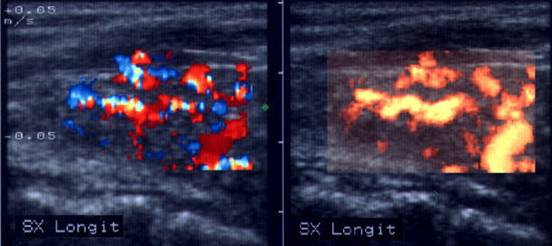

ecocolordoppler si powerdoppler- acelasi nodul

Vascularizatie interna, mai evidenta in powerdoppler.

Femeie 25 ani. Nodul unic in lobul stang, contur net, hipoecogen, respecta parenchimul din jur, neomogen, de 18x23x36 mm (7,5 cc).

Citoaspiratia cu ac subtire: nodul adenomatos.

Examen histologic postoperator: adenom trabecular fetal.

Acelasi caz. La doppler color - vascularizatie interna, mai evidenta in powerdoppler.